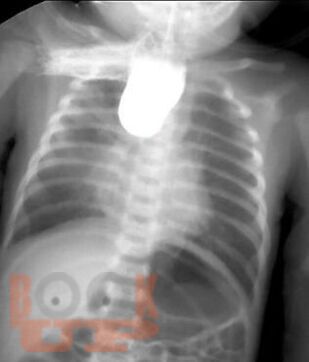

В пособии рассматриваются современные принципы диагностики и лечения хирургических заболеваний новорождённых и детей первого года жизни, возможных осложнений и исходов. Акцентируем внимание студентов на эмбриогенез, этиологию и патогенез, классификацию, клинические проявления и выбор методов лечения. Пособие содержит вопросы для самоконтроля и список литературы для дополнительного изучения.

Пособие подготовлено по дисциплине «Детские хирургические болезни» в соответствии с Федеральным государственным образовательным стандартом высшего профессионального образования для студентов V, VI курсов, обучающихся по основным образовательным программам - программам специалитета по специальности «Педиатрия» и для студентов, обучающихся по основным образовательным программам - программам специалитета по специальности «Лечебное дело».